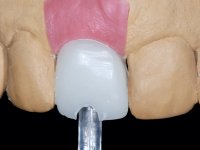

After performing an impression of the implant and making the models, we tested several rehabilitative options with the help of the implant brand planning kit. None proved capable. In this sense and as a resource solution, an innovative solution was proposed. It was proposed to make a milled Zr abutment with an appropriate design to receive a veneer that would hide the screw access hole. The veneer itself had a ceramic-coated Zr infrastructure. The goal was to achieve retention and strength by screwing the abutment and aesthetically solve the case with the veneer.

After the impression of the implant using a double-mix technique with double viscosity and the collection of shape and color information by the ceramist, we proceed with the work. In the model, a syn octa was placed over the implant, and a screw was placed on it to assess its emergence in relation to the incisal edge. Then, an adequate emergence profile in the artificial gingiva was prepared. A abutment with characteristics suitable for overbite and simultaneously capable of receiving a veneer was waxed on top of this scenario. This waxing gave rise to the manual milling of a very personalized abutment. An infrastructure in Zr was also made for the veneer with a very great adaptation to the abutment. On this infrastructure ceramics were placed. Ceramic fluorescence sought to compensate for the lack of fluorescence that Zr had and obviously further customize the aesthetics. The adhesive bridge was removed and the definitive work was placed. The syn octa was initially tightened with 35 N to the implant and then the Zr abutment was tightened over the syn octa with 15 N. The access hole was plugged and then the veneer was cemented with resin-reinforced glass ionomer. After 15 years, the patient returned to the consultation with tooth mobility. Fortunately, nowadays we have the possibility of having dynamic tightening wrenches that allow tightening screws with greater inclinations. An access cavity was made without damaging the incisal edge of the veneer. Tightening was done with a dynamic wrench with 15 N torque. The hole was covered with Teflon and filled with composite resin. This solution allowed the problem to be solved in a simple and economical way.